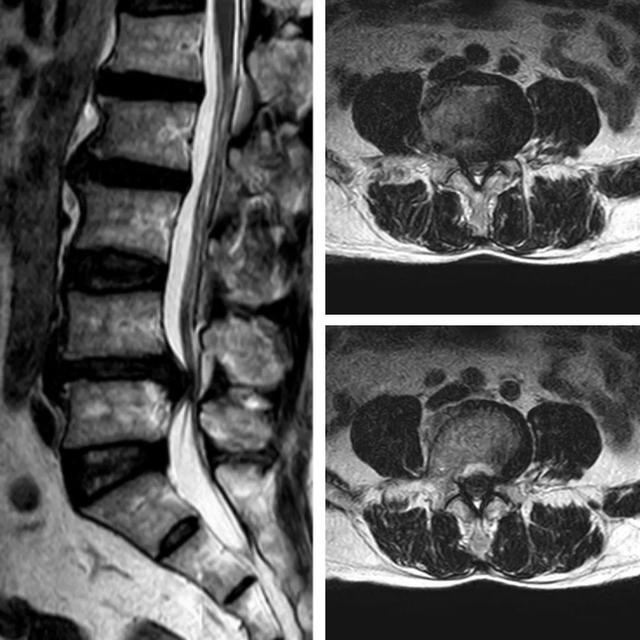

▲术前MRI见L4/5椎间盘突出,相应层面椎管狭窄

经过详细的病史询问、体格检查和影像学检查,患者最终确诊为腰椎滑脱症。考虑到传统开放手术创伤大、恢复慢、并发症较多等问题,团队决定为患者实施ULIF手术。